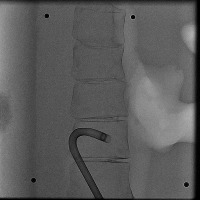

Healthcare Monitoring: "Cath" can be used in a real-time monitoring system within healthcare facilities. It can identify the position and type of a catheter tip in an x-ray, greatly helping healthcare professionals to assess the situation of patients having a lumbar puncture or spinal catheter implantation.

Medical Diagnosis: "Cath" can be used in the diagnosis of possible complications associated with catheter placements. Early detection of catheter displacement can prevent further complications.